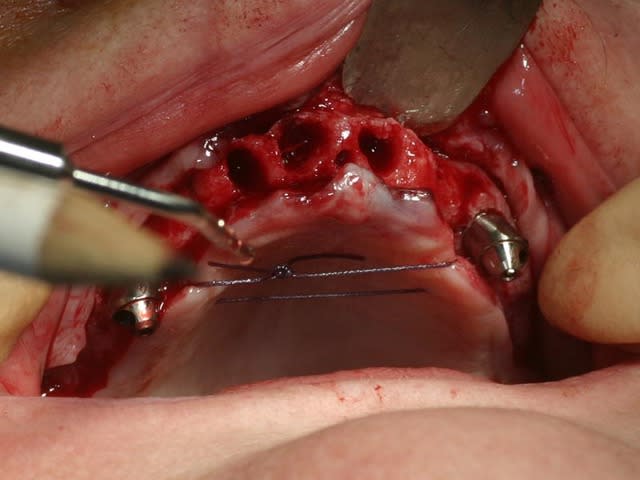

bon, toujours aussi speed je suis, mais après certaines réclamations, et malgrès ma réticence à poser un cas non "consolidé", voici en avant première mon premier all on 4, version photos ratées et non retouchées, mais... speed je suis je vous disais ;)

sto le bla bla, et pasons le diaporama... bon voyage au pays de la mise en charge immédiate totale au maxillaire de fille carole sur dame ginette, une patiente en or que j' adore, et pour qui je suis très très heureuse d' avoir pu réaliser cette chirurgie et la première étape prothétique.....